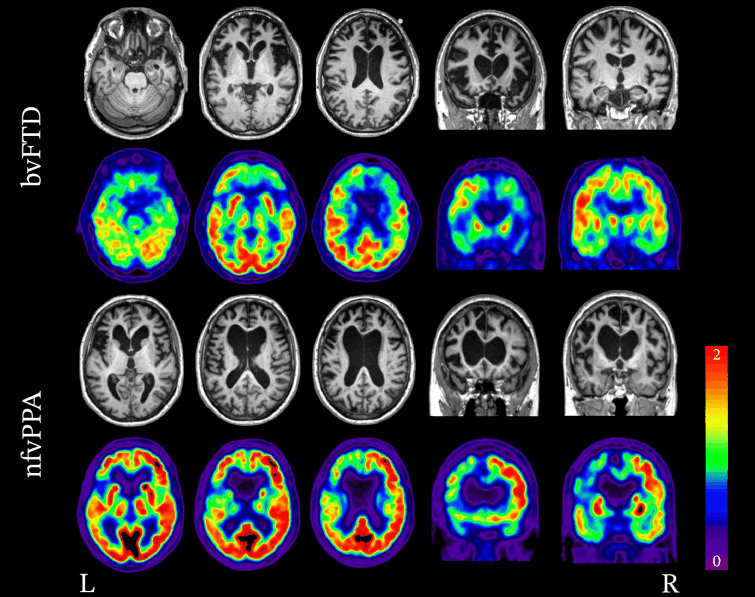

MRI is the key imaging modality for diagnosing FTD and should be ordered if a diagnosis of frontotemporal dementia is suspected.[104][106][Figure caption and citation for the preceding image starts]: Neuroimaging patterns associated with behavioural variant FTD (bvFTD) and nonfluent variant primary progressive aphasia (nfvPPA). Structural MRI and FDG-PET demonstrating the variability in patterns of atrophy and hypometabolism in FTD. In the case of bvFTD, significant bilateral frontal lobe atrophy and hypometabolism is seen. In the case of nfvPPA, atrophy and hypometabolism is lateralised and is greatly impacting the left frontal lobe more so than the right.Peet BT et al. Neurotherapeutics 2021 Apr; 18 (2): 728-52; used with permission [Citation ends].

FDG-PET/CT can help differentiate frontotemporal dementia from Alzheimer’s disease and dementia with Lewy bodies.[103][104][105] It is most helpful when combined with MRI.[104][Figure caption and citation for the preceding image starts]: Neuroimaging patterns associated with behavioural variant FTD (bvFTD) and nonfluent variant primary progressive aphasia (nfvPPA). Structural MRI and FDG-PET demonstrating the variability in patterns of atrophy and hypometabolism in FTD. In the case of bvFTD, significant bilateral frontal lobe atrophy and hypometabolism is seen. In the case of nfvPPA, atrophy and hypometabolism is lateralised and is greatly impacting the left frontal lobe more so than the right.Peet BT et al. Neurotherapeutics 2021 Apr; 18 (2): 728-52; used with permission [Citation ends].